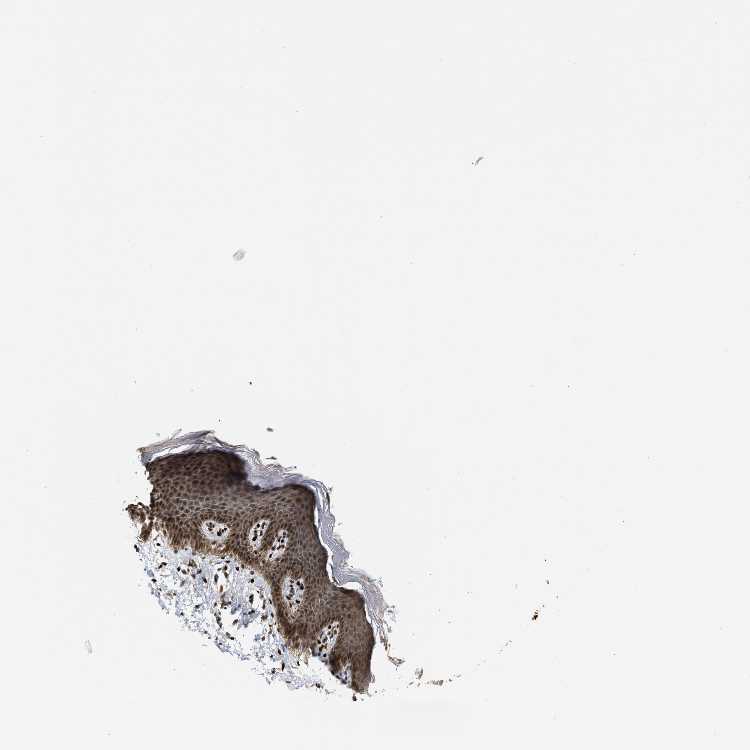

SKIN 1 - Antibody stainingi

Antibody staining in the annotated cell types in the current human tissue is reported as not detected, low, medium, or high, based on conventional immunohistochemistry profiling in selected tissues. This score is based on the combination of the staining intensity and fraction of stained cells.

Each image is clickable and will lead to virtual microscopy that enables deeper exploration of all samples and also displays staining intensity scores, fraction scores and subcellular localization as well as patient and tissue information for each sample.

Antibody HPA025958Antibody CAB020722

Langerhans MediumLow

Fibroblasts MediumMedium

Keratinocytes MediumLow

Melanocytes MediumLow

SKIN 2 - Antibody stainingi

Epidermal cells MediumMedium